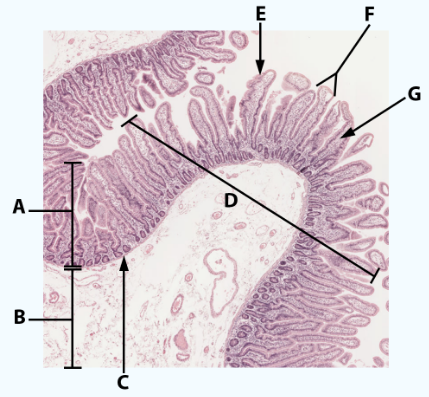

A

Mucosa

B

Muscularis mucosa

C

MALT

D

Lumen

E

Gastric pits: simple columnar epithelium

F

Gastric glands

G

Submucosa

H

Muscularis externa: oblique, circular, and longitudinal

area

Stomach